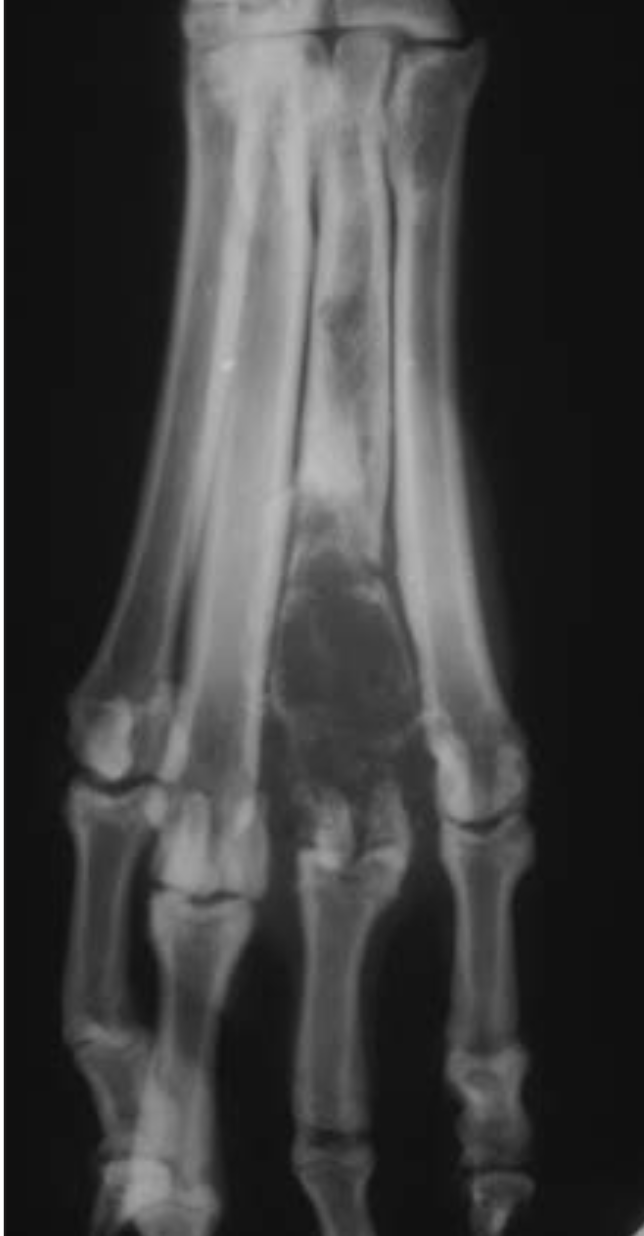

Thin brush-like

periosteal reaction of the abaxial

surface of metatarsals II andVinacaseof hypertrophic osteopathy.

Thick brush-like

periosteal reaction on the abaxial

surface of metacarpal V in a dog with hypertrophic osteopathy.